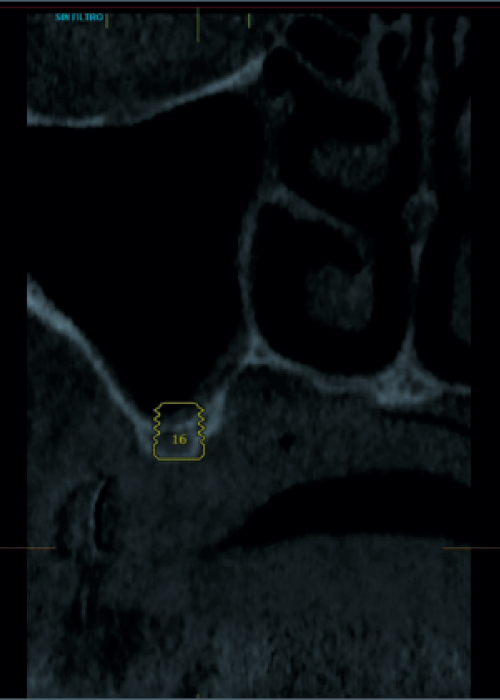

Elevación de seno transcrestal con inserción de implantes ultracortos de 4,5 mm de longitud en zonas maxilares posteriores con hueso residual menor o igual a 3 mm de altura

Implantes de 4,5 y 5,5 mm longitud insertados de forma directa en elevación crestal con hueso autólogo unido al Endoret-PRGF en alturas óseas residuales de 2-3 mm: estudio retrospectivo

Elevación de seno mediante abordaje transcrestal sin material de relleno con implantes extracortos (5,5 y 6,5 mm). Estudio retrospectivo con un seguimiento de 10 años